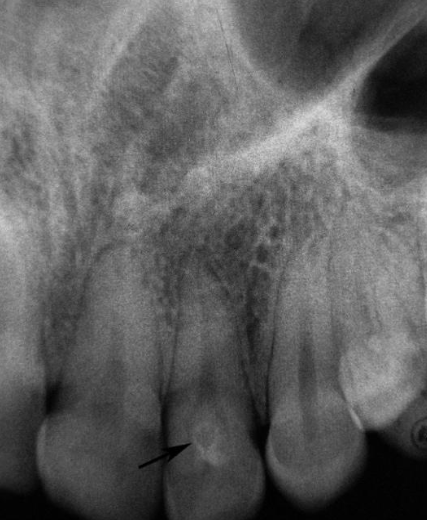

deep surface enamel invagination of the crown or root “tooth within tooth”; can be coronal (most frequent) or radicular

dens invaginatus “dens in dente”

“dens in dente” type I

invagination is confined to the crown

“dens in dente” type II

invagination extends below the CEJ

“dens in dente” type III

invagination may extend through the root

what is the dx?

dense invaginatus